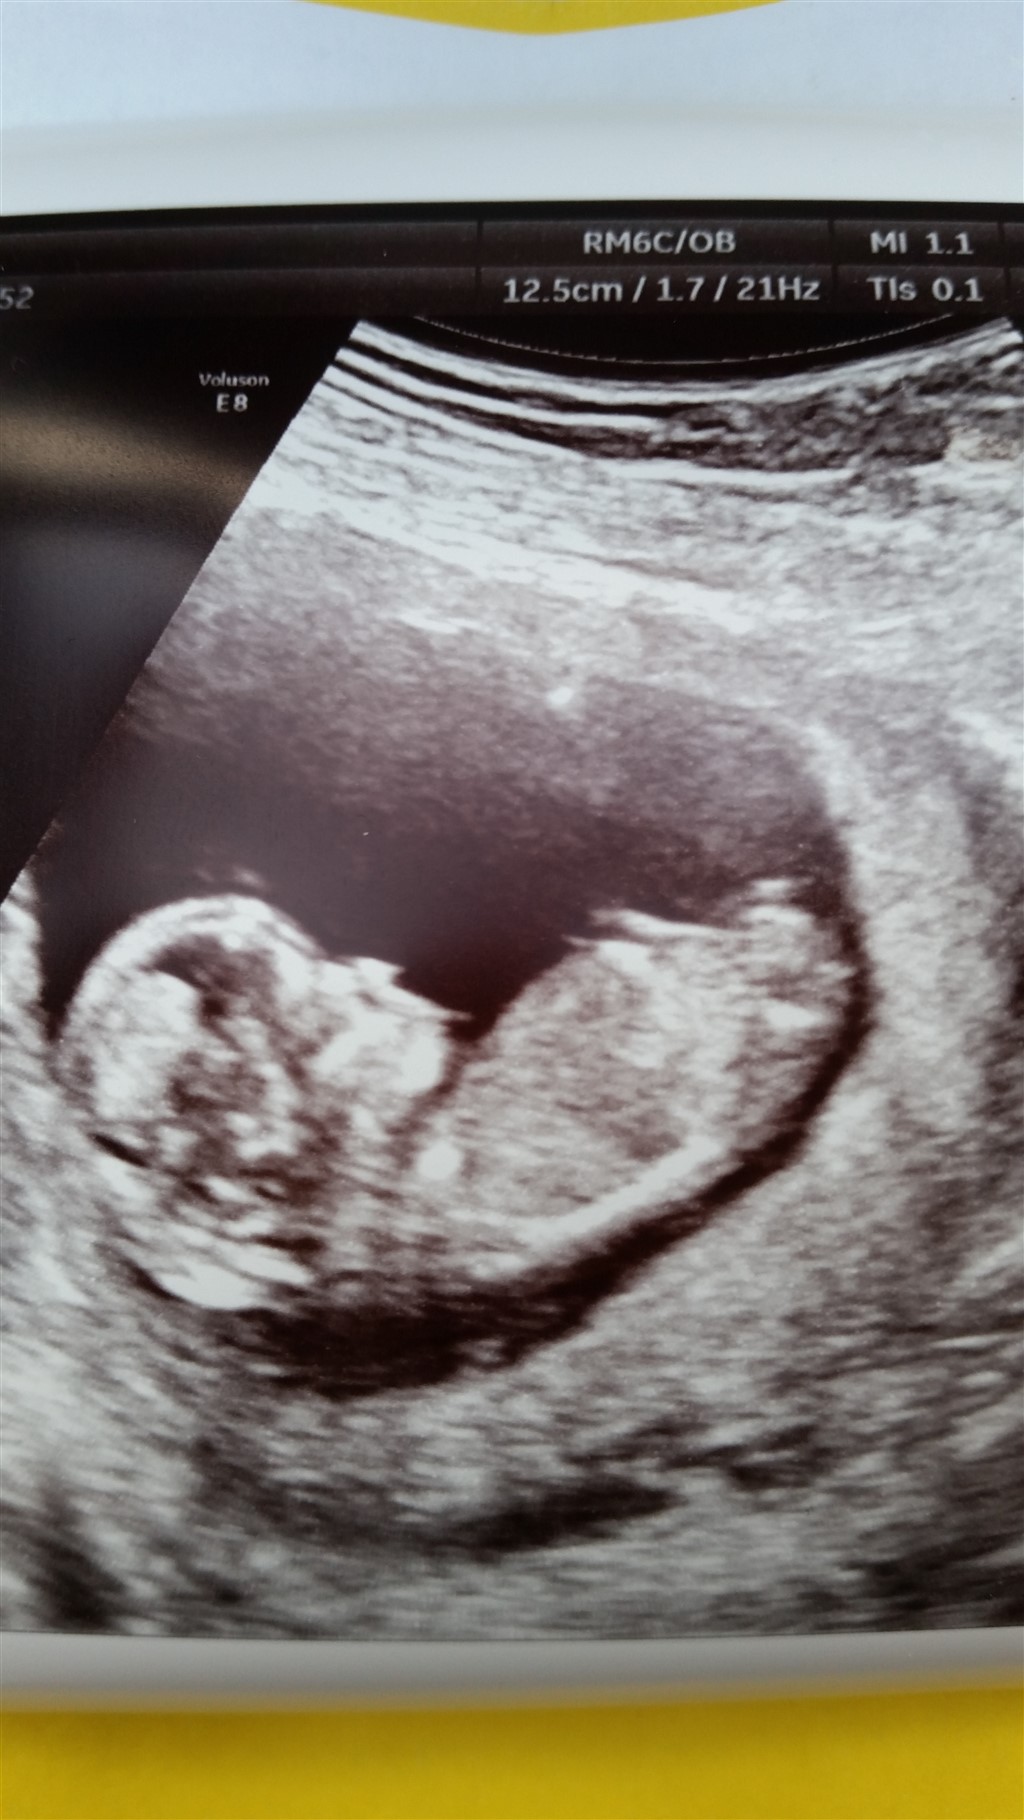

Så kom den længe ventede dag endeligt!

Kl. 8.20 skal jeg til nakkefold!